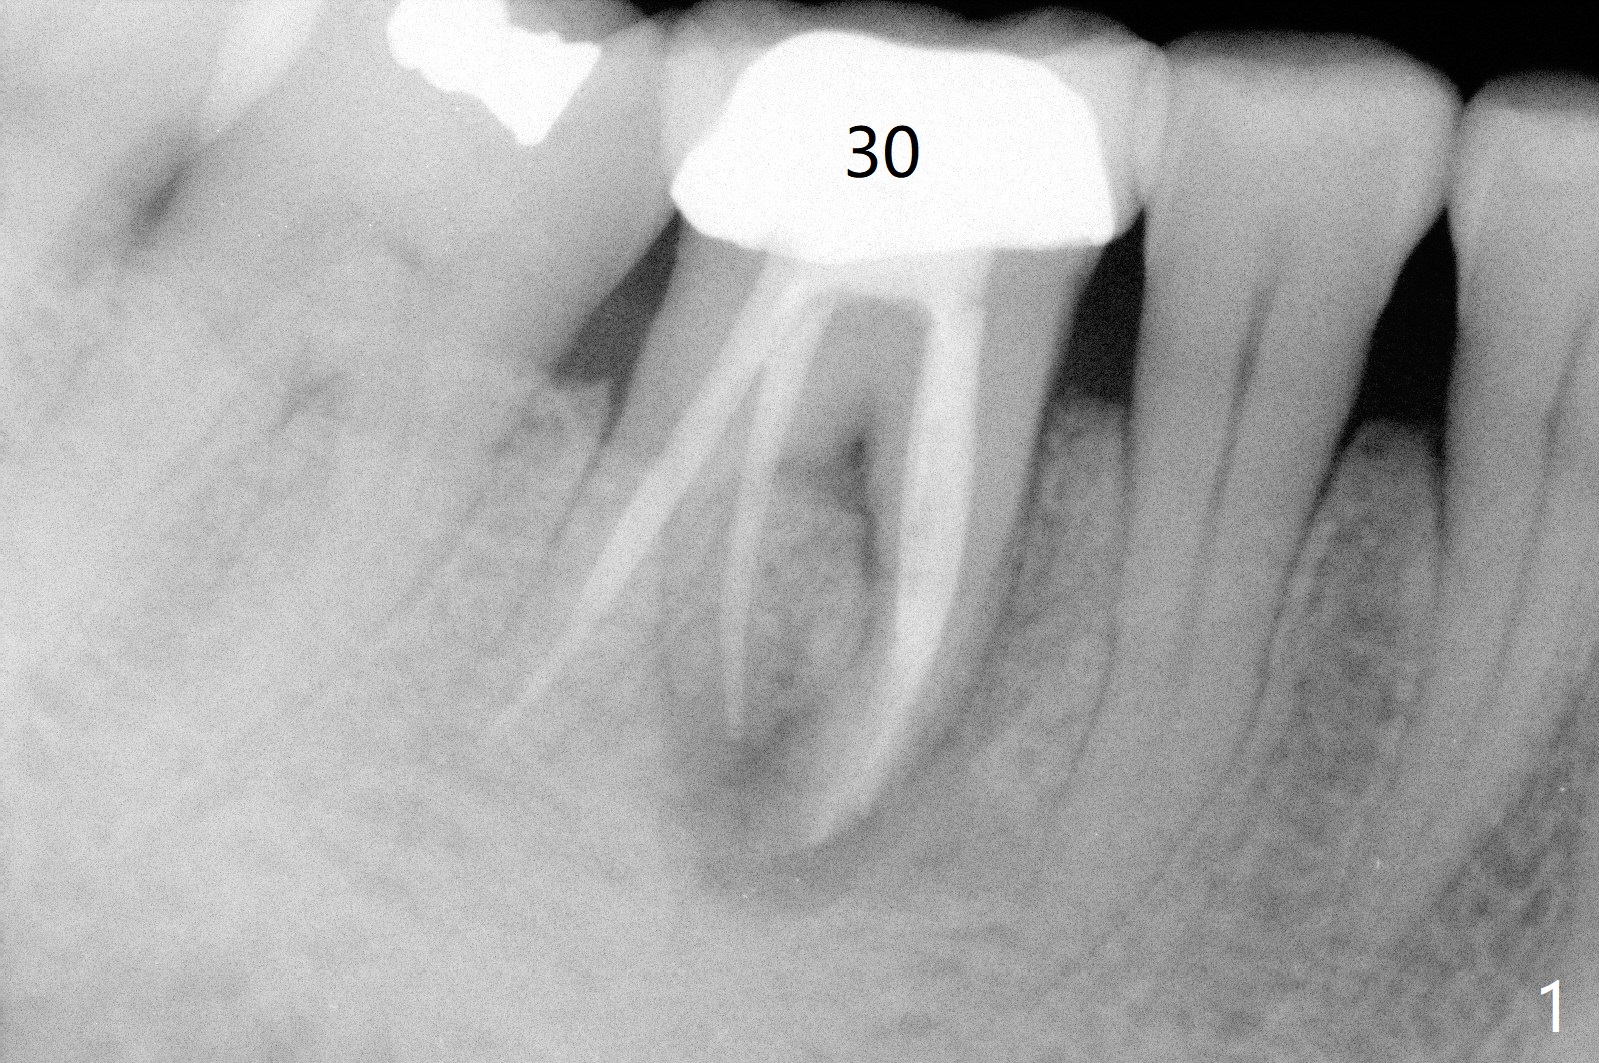

A 55-year-old woman has severe bone loss (Fig.1 with buccal and lingual fistulae) around the mesial (M in Fig.2) and distolingual (DL) roots. If there is a septum after extraction (Fig.3 S), osteotomy will be established in the septum to enhance primary stability (Fig.4). When the septum cannot be saved (Fig.5), osteotomy is to be initiated in the septal slope oblique (Fig.6 <). The osteotomy will be straightened once an entry is made (Fig.7). The initial osteotomy is slightly distal, since as osteotomy increases (Fig.8 blue), it tends to shift mesial (arrow). In addition, the apex of the 2nd bicuspid tilts distal (yellow dashed line). Depth of osteotomy is 20 mm (crest, Fig.9) or 18 mm (septum) so that 8 mm of the native bone can be obtained with 3 mm clearance from the Inferior Alveolar Canal (red dashed line). PRFx2 is required (seems not done).